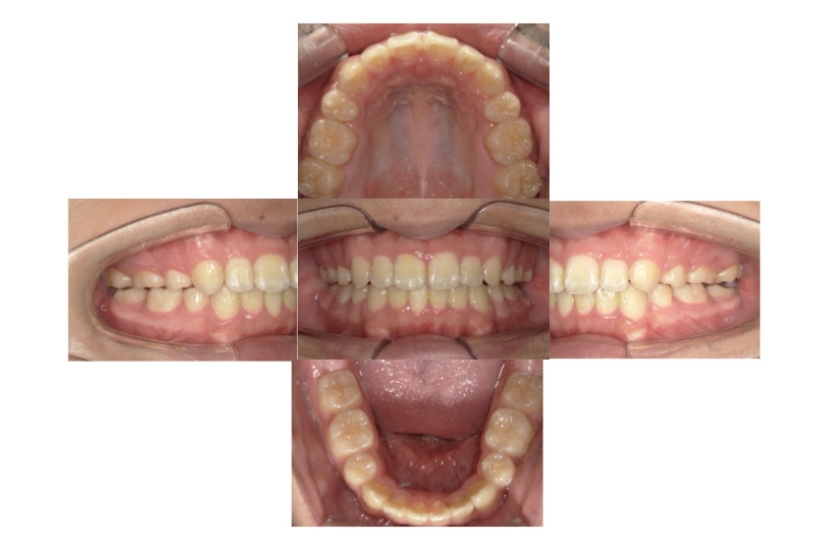

BEFORE

AFTER

上下顎叢生(上下の前歯のガタガタ)のケースです。

装置はラビアル(上下表側)で、上下顎の小臼歯を4本抜歯を行っています。抜歯したスペースを利用し、上下の前歯の後方移動と叢生(ガタガタ)の改善を行っています。口元の出っ張りを改善するため、歯科用アンカースクリューを使用して前歯の後方移動を行いました。

主訴 上下の前歯のガタガタを治したい。 口元を引っ込ませたい。

年齢・性別 22歳 女性

お住まいの地域 東京都大田区

治療方針 抜歯スペースを利用して上下前歯の叢生(ガタガタ)の改善

抜歯部位 上下顎左右第一小臼歯

使用装置 ラビアル(上下表側)、顎間ゴム、歯科用アンカースクリュー

治療期間 2年1か月

治療回数 20回